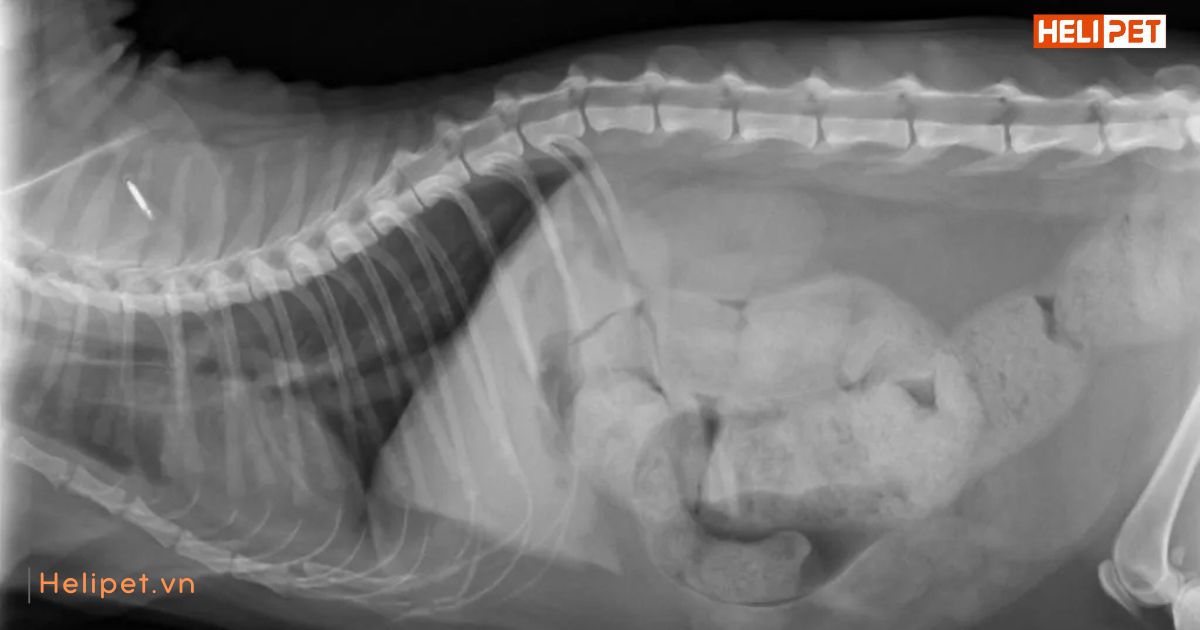

Hình ảnh chụp X-quang mèo bị táo bón